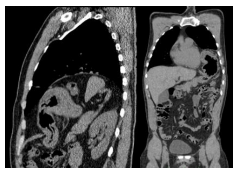

Em relação ao caso apresentado na questão

anterior, após estabilização do paciente, ele

foi submetido à tomografia de tórax cujo

achado mais significativo aparece na

seguinte imagem. Com base no exposto,

assinale a alternativa correta.